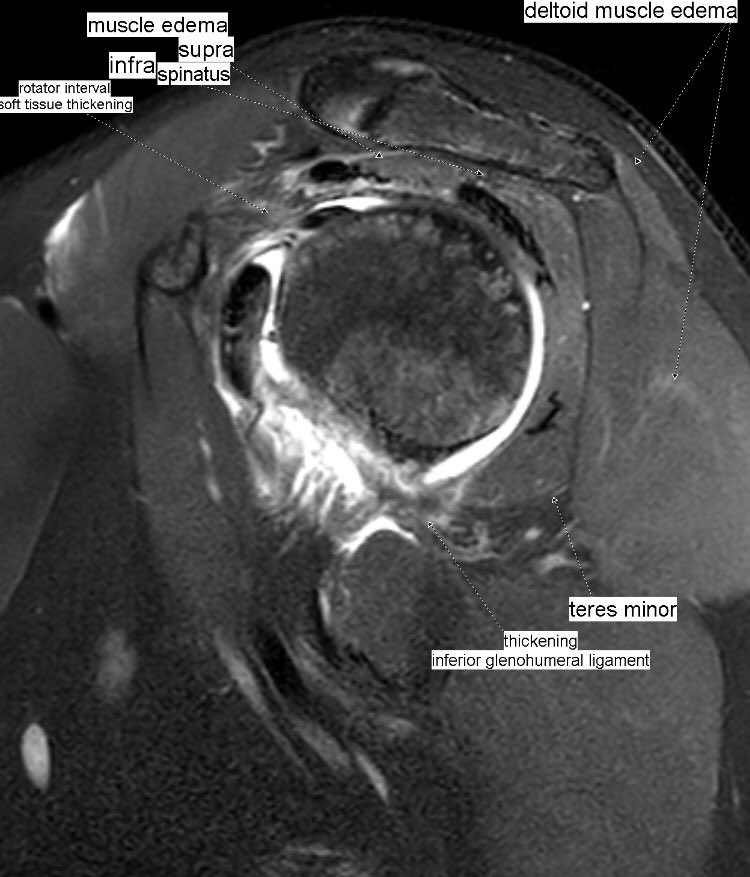

Edema + patchy fatty infiltration of supraspinatus, infraspinatus, deltoid and teres minor muscles. Parsonage-Turner syndrome (acute brachial plexus neuritis) of suprascapular + axillary nerves. Associated adhesive capsulitis.

#MSKrad#shoulder#orthotwitterpic.twitter.com/1C0f9g30Ad